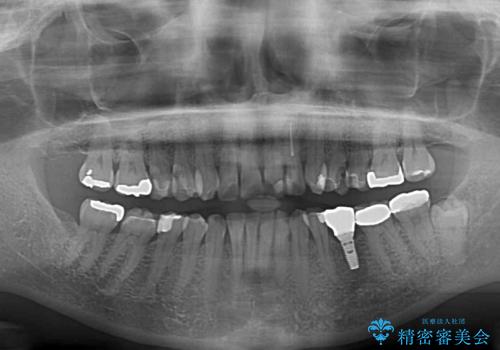

- 目立つ銀歯やむし歯、前歯のデコボコを気にして来院された患者様です。

むし歯治療は、症状のある歯を矯正治療前に処置し、概ね歯列が整ったところで残りのは全て処置し、最後にインビザラインで歯列を仕上げることで、無駄なく治療を進めて行くこととしました。